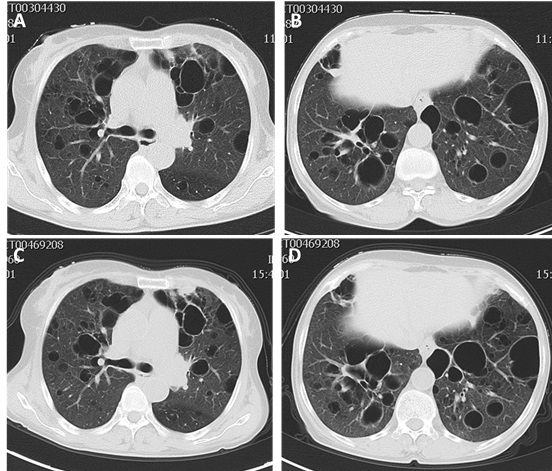

A 56-year-old woman was hospitalized in Qilu Hospital of Shandong University in October 2014 because of a history of xerostomia, xerophthalmia, dry systemic skin for six years and intermittent cough, little white sputum , worsening dyspnea for three years. Physical examination revealed vesicular breath sounds in bilateral lungs. The remainder of physical examination was normal. Her laboratory work showed white blood cell (WBC) count 2100/mm3 (normal 4000-10000/mm3), neutrophil (NEU) count 1410/mm3 (normal 1800-6300/mm3), lymphocyte count 610/mm3 (normal 1100-3200/mm3), monocyte count 90/mm3 (normal 100-600/mm3), erythrocyte count 3.44×1012/L (normal 3.8-5.1×1012/L), erythrocyte sedimentation rate (ESR) 72mm/h (normal 0-18mm/h). Rheumatism laboratory examination showed anti-nuclear antibody (ANA) 1:640 positive (normal < 1:80), positive anti-SSA antibody and anti-SSB antibody (normal negative), quantitative anti-bodies to double-stranded DNA (dsDNA) 49.55 IU/ml (normal < 100IU/ml). Humoral immune test showed IgG 35 g/L (normal 7-16g/L), IgA 9.77 g/L (normal 0.7-4 g/L), C3 (complement component 3) 0.84 g/L (normal 0.9-1.8g/L), C4 (complement component 4) 0.093 g/L (normal 0.1-0.4g/L) (Table 1). Schirmer’s test showed right eye 2mm/5min and left eye 5mm/5min (normal 10-45mm/5min). Chest computed tomography (CT) showed bilateral diffuse cystic changes with a wide variation in cyst size (Figure 1A-1B). The diameter length of vesicles ranged approximately from 3.2mm to 50.2mm. Cysts were thin walled and asymmetrically distributed throughout the lung. She was diagnosed pSS with diffuse cystic lung changes. After 8 days therapy of intravenous methylprednisolone (40mg qd), hydroxychloroquine (200mg bid) and antibiotics of cefuroxime (1.5g q12h), she felt xerostomia, xerophthalmia and respiratory symptoms relieved. The blood routine indexes also showed improvement from WBC count 2100/mm3 to 3640/mm3 and from NEU count 1410/mm3 to 2399/mm3. She was discharged home and had been taking prednisone (50mg qd) with hydroxychloroquine (200mg bid). She gradually reduced dosage of prednisone to zero, and stopped taking all drugs on Feb 2016.

CT showed asymmetrically diffuse cystic changes with a wide variation in cyst size and distribution, which was almost unchanged from 2014 (Figure 1C-1D). Schirmer’s test of her eyes revealed both eyes 0 mm/5min. Secretions of saliva were reduced. Biopsy of lower lip revealed chronic inflammation and lymphocytes infiltration of minor salivary glands (Figure 2). Pulmonary function test showed total lung capacity (TLC) 4.51L (predicted value 4.64L), vital capacity (VC) MAX 2.32L (predicted value 2.67L), forced vital capacity (FVC) 1.96L (predicted value 2.58L), forced expiratory volume in one second (FEV1) 1.34L (predicted value 2.17L), FEV1/predicted FEV1 value (FEV1%) 61.9%, FEV1/forced capacity ratio (FEV1/FVC) 68.31%, and diffusion function test showed carbon monoxide transfer factor in single breath (TLCO SB) 7.22 ml/min/mmHg (predicted value 21.78 ml/min/mmHg).

Figure 1: A.-B. Chest high resolution computed tomography (HRCT) images in 2014 showing bilateral diffuse thin walled cystic changes with a wide variation in cyst size and distribution. C.-D. Chest HRCT images in 2016 which were almost unchanged from 2014.

SS is a chronic systemic inflammatory disease with lymphocytic infiltration of exocrine glands. SS can exist as a unique presence (pSS) or in combination with other systemic diseases (sSS). While salivary and lacrimal glands are most ordinarily involved, impaired mucosal defense and glandular dysfunction inside of the lung may make it more vulnerable to pulmonary inflammation [20]. The case reported here was diagnosed Sjögren’s syndrome in 2014 according to the American and European Consensus Group classification criteria (AECG-criteria) [27], and then developed SLE in 2016 based on the 2012 revision classification criteria for SLE [28]. HRCT images in 2014 and 2016 showed asymmetric multiple cysts of varying size and distribution in both lungs, and did not present an obvious progression in the size, number and distribution of cysts.